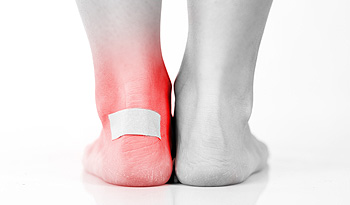

Why Do Blisters on the Feet Develop?

When the upper layer of skin has been damaged, the body’s natural defense mechanism can form a blister for protection. It is defined as a small area that resembles a bubble and is filled with liquid that cushions that raw skin as the healing process occurs. Blisters generally develop from excessive friction and can be quite painful and uncomfortable. Wearing shoes and socks that do not fit correctly is a common cause of blisters. There are some patients who have specific medical conditions that can cause blisters. These can include eczema and psoriasis, in addition to developing an allergic reaction to an insect bite. It can be beneficial to cover the blister with a protective covering while accomplishing daily activities, which may help to prevent premature popping and draining. If you have a blister on your foot, please speak with a podiatrist who can offer you treatment techniques that can possibly avoid an infection from developing.

Blisters are prone to making everyday activities extremely uncomfortable. If your feet are hurting, contact Roy Moeller, DPM of Foot & Ankle Physicians West. Our doctors can provide the care you need to keep you pain-free and on your feet.

Foot Blisters

Foot blisters develop as a result of constantly wearing tight or ill-fitting footwear. This happens due to the constant rubbing from the shoe, which can often lead to pain.

What Are Foot Blisters?

A foot blister is a small fluid-filled pocket that forms on the upper-most layer of the skin. Blisters are filled with clear fluid and can lead to blood drainage or pus if the area becomes infected.

How Do Blisters Form?

Blisters on the feet are often the result of constant friction of skin and material, usually by shoe rubbing. Walking in sandals, boots, or shoes that don’t fit properly for long periods of time can result in a blister. Having consistent foot moisture and humidity can easily lead to blister formation.

Prevention & Treatment

It is important to properly care for the affected area in order to prevent infection and ease the pain. Do not lance the blister and use a Band-Aid to provide pain relief. Also, be sure to keep your feet dry and wear proper fitting shoes. If you see blood or pus in a blister, seek assistance from a podiatrist.